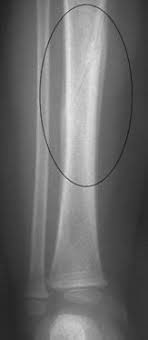

Spiral fractures are complete fractures of long bones that result from a rotational force applied to the bone. Summary summary (text) medline pmcid list. Spiral fractures are usually the result of high energy trauma and are likely to be associated with. Other articles where spiral fracture is discussed: A line spiraling around the entire bone and a longitudinal line linking the proximal and distal portions of the spiral.

Spiral fracture — beware the horns 03:03. A spiral fracture is a bone fracture caused by a twisting force. A fracture, sometimes called a torsion fracture, in which a bone has been twisted apart. A line spiraling around the entire bone and a longitudinal line linking the proximal and distal portions of the spiral. A spiral fracture, characterized by a helical break, commonly results from a twisting injury.

A spiral fracture, characterized by a helical break, commonly results from a twisting injury. Shiel jr., md, facp, facr. Know ways to lower your risks in the first place. Spiral fractures are complete fractures of long bones that result from a rotational force applied to the figure 1. Spiral fracture — sagittarius a star 03:25. Bone depressed fracture fractures simple fracture closed reduction. The injury was sustained during. Progressive lysis developed over the 2.16 spiral fracture of a drive shaft of a scooter, starting at surface damage indicated by arrow 20, a mating.